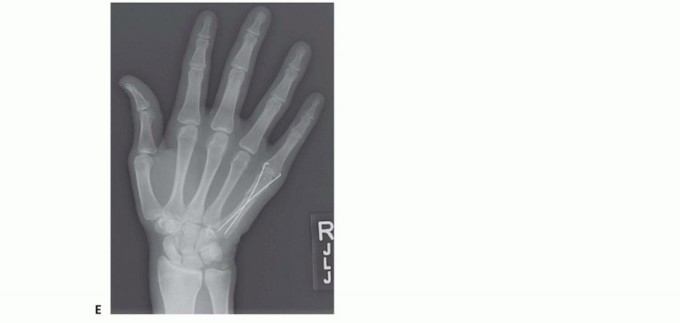

FIG 3 • A. Fracture of the neck of the fifth metacarpal with a flexed, apex dorsal angulation (boxer's fracture). B. Torsional injuries lead to long oblique fractures with a risk for malrotation. C. Short transverse fracture from a direct impact. D. Crush injuries can lead to a combination of injuries with an increased risk of compartment syndrome and significant stiffness. The shortened fourth metacarpal pulls the head of third metacarpal in a proximal and ulnar direction through deep transverse metacarpal ligament. E. Neglected fight bite injury ultimately leading to loss of the metacarpal head. Crush injuries can lead to comminuted fractures with significant soft tissue injuries and a heightened risk of compartment syndrome (FIG 3D).

Metacarpal fractures are mainly affected by shortening and rotation. The effect of these two components is minimized in the central metacarpals due to the stabilizing effect ofP.457the deep transverse metacarpal ligaments and the bordering intact metacarpals. This stabilizing effect is lost incases of multiple metacarpal fractures and more severe injuries (see FIG 3D).Shaft fractures of the third and fourth metacarpals tend to do well with minimal intervention. Border metacarpals are more prone to shortening and rotation.Every 2 mm of shortening of the metacarpal can lead to a 7-degree lag at the MP joint.12Fractures of the metacarpal neck typically result in apex dorsal angulation, which may lead to significant shortening. The increased mobility afforded by the ulnar CMC joints allows more tolerance of angulation in the ulnar metacarpals (fourth and fifth). Whereas some have accepted up to 70 degrees, most authors haverecommended intervention if the angulation exceeds 30 to 40 degrees.4,6,9 The radial metacarpals (second to third) have stiffer CMC joints, and correspondingly, the tolerance for angulation is reduced to only 10 to 15degrees.7Thumb metacarpal extra-articular base and shaft fractures can easily tolerate 30 degrees of angulation due to its highly mobile CMC joint.1Fractures of the metacarpal head with a significant gap or step-off, or fractures that involve a significant portion of the articular surface, should be considered for open reduction and stabilization.2